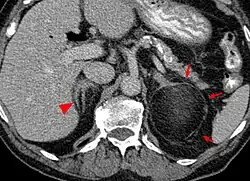

Diagnosis

Most myelolipomas are unexpected findings on CT scans and MRI scans of the abdomen. They may sometimes be seen on a plain X-ray films.[4]